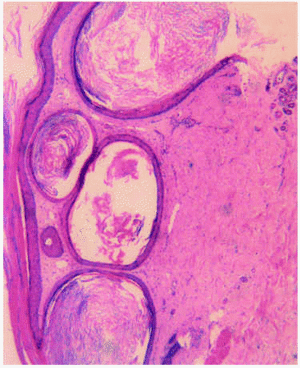

Una mujer de 58 años acudió a nuestra consulta por presentar, desde hacía 3 meses, varias placas eritematosas con quistes miliares agrupados en su superficie, localizadas a lo largo de las cuatro extremidades. Negaba el uso de ningún cosmético y no recordaba ningún traumatismo previo o quemadura. Como antecedentes personales, no refería alergias medicamentosas conocidas ni hábitos tóxicos. Padecía leucemia mieloide crónica de 6 años de evolución, y había iniciado tratamiento paliativo con 6-mercaptopurina un mes antes de que aparecieran las lesiones cutáneas por progresión de su enfermedad hematológica. Asimismo, debido a un síndrome ansioso-depresivo recibía citalopram desde hacía varios años. En la exploración física se apreciaban varias placas eritematosas, ovaladas, bien definidas, de 3 cm de diámetro máximo, en cuyo interior había quistes miliares confluentes (fig. 1). Presentaba asimismo algunos quistes miliares aislados en la región facial. El resto de la exploración fue normal. Se efectuó biopsia cutánea que, teñida con hematoxilina-eosina (fig. 2), mostró varios quistes alineados por epitelio estratificado, llenos de queratina, que formaban capas concéntricas laminadas. No se encontraron más alteraciones.

Fig. 2.--Quistes alineados por epitelio estratificado con queratina concéntrica. (Hematoxilina-eosina, x20.)